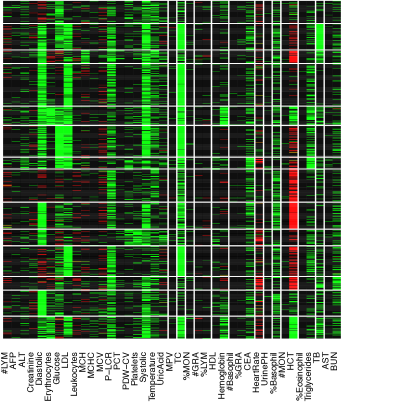

The data contain blood test results measured on 39 testing items which are listed in Table 1. Figure 1(a) shows the empirical correlation structure of the testing items as a heatmap with green, black, and red colors indicating positive, negligible and negative correlations. With appropriate ordering of the test items, one can see some patterns on the upper-left corner of the heatmap. However, the patterns seem vague and have no clear interpretation. The heatmap of the standardized data is shown in Figure 1 with green, black and red colors indicating values above, near and below the average. Next we cluster the data using a K-means algorithm with (the number of latent diseases identified in later model-based inference), applied to both, rows and columns of the data matrix. The clusters find some interesting structures. For example, indexing the submatrices in the heatmap by row and column blocks, the values in block (9,9) tend to be above the average, whereas the values in the block (1,4) tend to be below the average. However, there are at least two difficulties in interpreting the clusters as latent diseases. Firstly, there is no absolute relationship between the normal range of a testing item and its population average. A deviation from the average does not necessarily indicate an abnormality. Likewise, average values of testing items, especially those related to common diseases such as hypertension, are not necessarily within the normal range. For instance, the mean and the median of systolic blood pressure in our dataset are 147 mm Hg and 145 mm Hg, both of which are beyond the threshold 140 mm Hg for hypertension (the high blood pressure values might be related to the elderly patient population). Secondly, the exploratory analysis with K-means does not explicitly model patient-disease relationships and symptom-disease relationships. For example, one may be tempted to interpret each column block as a latent disease. As a consequence, each testing item has to be associated with exactly one disease and the patient-disease relationship is unclear. If instead, we define a latent disease by the row blocks, then each patient has to have exactly one disease and the symptom-disease relationship is ambiguous.

We can slightly improve interpretability by incorporating prior information. Specifically, each testing item comes with a reference range which we use to define symptoms: a symptom is an item beyond the reference range. In essence, we convert the original data matrix into a ternary matrix which is shown in Figure 1. The first difficulty is resolved but the second difficulty remains. For instance, the 6th column seems to suggest a disease with elevated total cholesterol and low density lipoproteins, which is also found in our later analysis with the proposed DFA. However, just as in Figure 1, it is hard to judge which blocks meaningfully represent latent disease since patient-disease relationships and symptom-disease relationships are not explicitly modeled. Besides the requirement of specifying the number of clusters, K-means is unsuitable for the task that we are pursuing in this paper.

Alternatively, instead of discretization, we can scale and center test items at the midpoint of each reference range. We show the heatmap in Figure 1 where the rows and the columns are arranged in the same way as in Figure 1. However, just as previous cases, the same limitation of interpretability still applies.